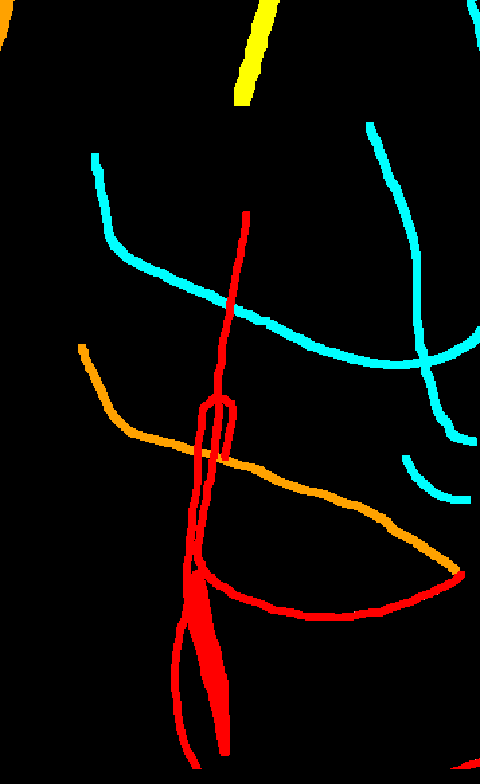

Automated catheter detection is a challenging task. Although most catheters have a radiopaque strip to facilitate detection, the strip may become less apparent depending on the projection angle. Catheters maybe confused by other similar linear structures like ECG leads and anatomy including ribs. Additionally, portions of catheters can be occluded by anatomical structures given that radiographs are a 2D projection of a 3D structure. For example, when a NGT is placed within the oesophagus, the catheter itself becomes less apparent due to the high density of the adjacent vertebrae. Finally, the number and type of catheters that could possibly appear in pediatric X-rays are unknown a priori. The catheters may be intertwined with each other thus making simple line tracing methods fail. Figure 1 gives three sample pediatric X-ray images with some common catheters highlighted in different colors.

To alleviate this annotation problem in catheter detection, we proposed to use X-ray images with simulated catheters by exploiting the fact that catheters are essentially tubular objects with various cross sectional profiles. To be more specific, a synthetic 2D projection of a catheter is generated by first simulating a horizontal catheter profile and then using it as a brush tip to draw along a B-spline path. This generated catheter is then composited with an X-ray image serving as the training data. Another contribution of this work is a segmentation network that can inherently take into account multi-scale information. This network adopts a UNet-style form and contains a recurrent module that can process inputs with increasing scales111Our code is available at https://github.com/xinario/catheter_detection.git.. We have empirically shown that by iterating through the scale space of the input image, higher recall is achieved as compared to using a single scale. Details about the methods are discussed in Section 3. Three sample detection results are shown in Figure 1.

The test dataset is collected locally and only contains frontal chest-abdominal X-rays from patients < 4 weeks old. This is the most common radiograph obtained to confirm placement of catheters such as UACs and UVCs in neonates. Currently, the test set has 35 fully labeled images with different catheter types with sample images previously shown in Figure 1. All the annotated catheters (lines excluding ECG leads) are treated as the same class in the detection.